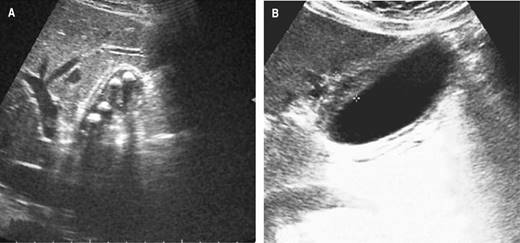

Upon admission, all patients underwent imaging studies for suspected acute cholecystitis (abdominal ultrasonography and or abdominal tomography). In all patients, the gallbladder wall thickening of more than 5 mm (mean: 8.96 mm, range: 5-16 mm) was corroborated, and signs of acute cholecystitis (criteria TG-18) or structural alterations were ruled out. Differences between acute cholecystitis and gallbladder edema in the abdominal ultrasound are shown in Figure 1, and differences in the CT scan are shown in Figure 2, respectively.

Figure 1: Abdominal ultrasound shows differences between acute cholecystitis and gallbladder wall thickening without cholecystitis. A) Wall thickening of the gallbladder due to acute cholecystitis with multiple lithiasis. B) Simple gallbladder edema due to dengue without cholecystitis.